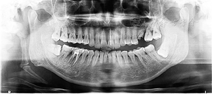

(1)临床资料:患者男性,38岁,因"下颌右侧第一磨牙疼痛2天"于2018年11月14日就诊于郑州大学第一附属医院口腔科门诊。经曲面体层X线片检查,发现下颌骨右侧多生骨两块(图1)。查体:患者一般状况较好,面部对称,双侧下颌角无红肿,无压痛,咽部黏膜正常,无张口受限,颈部活动无受限,右侧颈部下颌骨下方触及长条形硬物,质地坚硬,按压无痛感。患者自述夜间睡眠时张口呼吸,打鼾较重,但无呼吸暂停,无其他自觉症状。锥形束CT(Kavo 3D Exam,美国)检查显示,右侧茎突舌骨韧带可见明显分节的三段骨(图2),第一段骨长21.26 mm,与颞骨下关节窝形成关节(图3),第二段骨长39.79 mm,与第三段骨形成关节,第三段骨长28.16 mm,与舌骨体相距4.78 mm,未见右侧舌骨小角。左侧茎突舌骨韧带可见两段骨(图4),第一段与颞骨相连,是1块长53.74 mm的巨大茎突,第二段骨长12.97 mm,与茎突相距29.33 mm,与左侧舌骨小角相距2.36 mm。患者左侧舌骨大角向内侧弯曲(图5),两舌骨大角游离端内缘之间距离(设为a线)为31.55 mm,舌骨体内缘至a线的距离为28.71 mm,颈椎椎体前缘至a线的距离为3.51 mm。两舌骨大角游离端与第四颈椎之间各有一块直径约4 mm大小的类圆形小骨(图5),左侧小骨距左侧舌骨大角1.46 mm,距第四颈椎体中部外侧缘4.07 mm,右侧小骨距右侧舌骨大角1.00 mm,距第四颈椎右侧横突(横突孔位置)前缘3.75 mm。